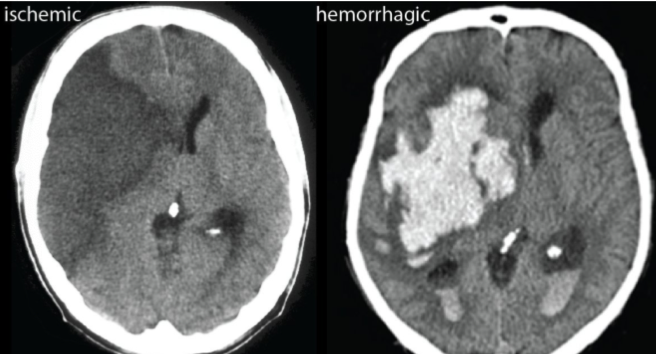

what are the 2 main types of stroke- which is more common?

Ischaemic (85%)= Occur when blood supply in a cerebreal vascular territory is reduced secondary to stenosis or complete occlusion of a cerebral artery

Haemorrhagic (15%)= when there is a rupture of the cerebrospinal artery

what is the first investigation that should be done if suspected stroke and why?

CT- to distinguish between ischaemic and haemorrhagic

how will ischaemic stroke and haemorrhagic stroke present differently on CT?

haemorrhagic- blood looks white

iscahemic- ischaemia looks dark